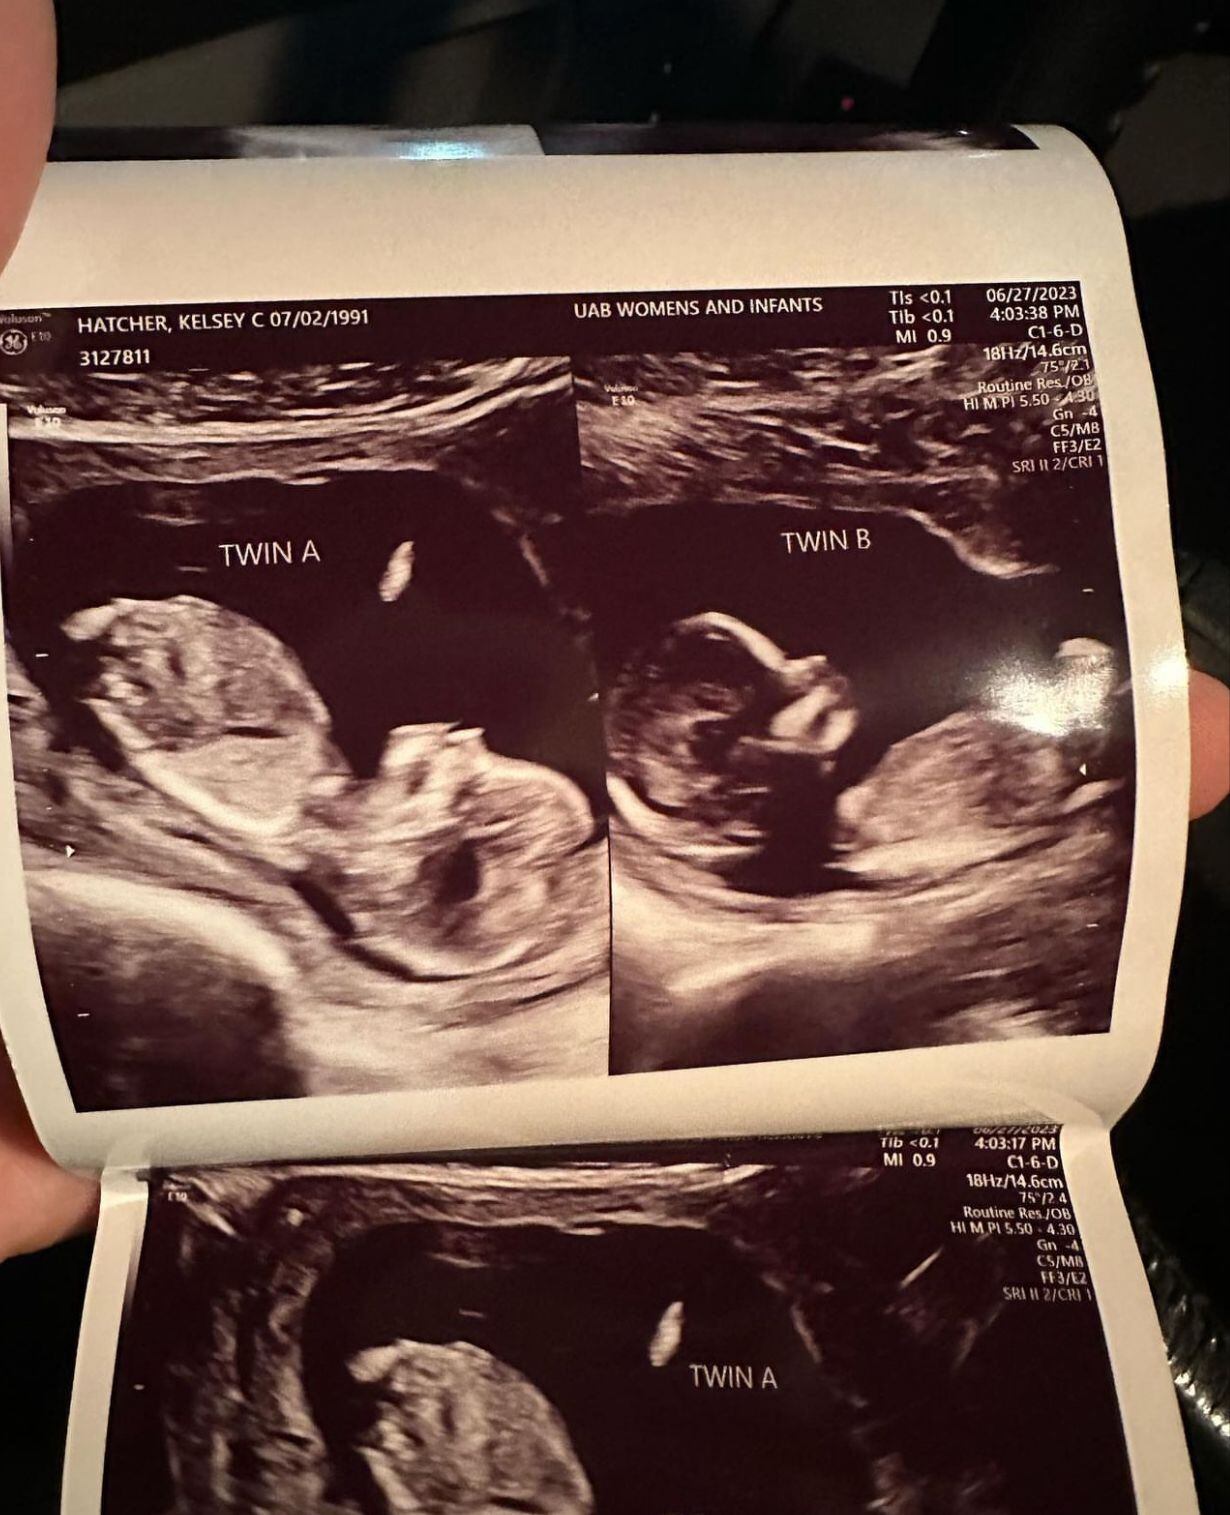

Kelsey Hatcher, de Alabama, en Estados Unidos, nació con dos úteros funcionales y cada uno con su propio cuello uterino. Tras completar su ultrasonido inicial, compartió la emocionante noticia con su esposo Caleb: que no solo estaba embarazada, sino que estaba embarazada en ambos órganos.

Kelsey dijo que ella y su esposo durante su cita rutinaria de ultrasonido de ocho semanas, en mayo, descubrieron que no solo estaba esperando gemelos, sino que también había un feto presente en cada uno de sus úteros.

La masajista y madre de tres hijos conoce su rara enfermedad llamada “útero didelfo”, en la que una persona nace con dos úteros y dos cuellos uterinos, desde que tenía 17 años. “¡Quedamos impresionados! Durante esa primera ecografía nos reímos muchas”, dijo Kelsey en una publicación de Instagram.

El Dr. Richard Davis, especialista en embarazos de alto riesgo de la Universidad de Alabama, dijo: “Un doble cuello uterino o doble útero está muy por debajo del 1 %, tal vez tres de cada 1.000 mujeres podrían tener eso.

“Y, además, la probabilidad de que tengas un gemelo en cada cuerno es realmente loca”.